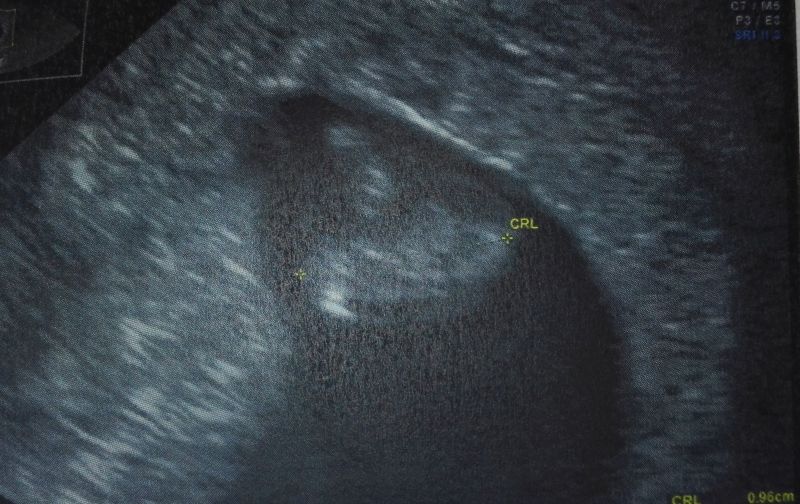

Śliczna Fasolka [emoji7] Gratuluję [emoji173]Poznajcie Moje 1cm Maleństwo ( 0,96mm dokładnie )serduszko 132 uderzenia

wg USG ,6tydz 3 dzień (wg om 7tydz 4d)